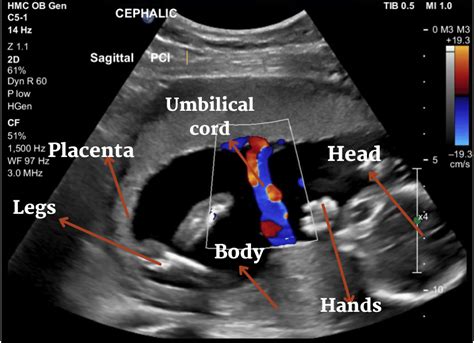

WebA Doppler scan is a non-invasive ultrasound that assesses your baby’s growth and wellbeing and identifies any health concerns. It uses high-frequency sound waves that. WebThe state or city where you live – Areas with a higher cost of living will likely charge more for your ultrasound procedure. For instance, according to Healthcare. WebDuring labor, fetal heart monitors can show your health care team how your baby’s heartbeat reacts to contractions. That can give a sense of how she’s coping with the stresses of.

WebDoppler ultrasound of fetal blood vessels in normal pregnancies. One of the main aims of routine antenatal care is to identify babies who are not thriving in the womb. It is possible. WebColor doppler is a non invasive diagnostic test making use of sound waves to assess the health of internal body organs. It is a relatively newer and advanced method of. WebWhile some brands claim that their fetal dopplers can detect heartbeats from 9 weeks into the pregnancy, others claim they only work from around week 16. Some.

WebA Doppler ultrasound is an imaging test that uses sound waves to show blood moving through blood vessels. A regular ultrasound also uses sound waves to create images of. WebIf you have an electronic fetal heart rate monitor, also known as a fetal Doppler, you can check your baby's heartbeat during your pregnancy. The fetal Doppler.